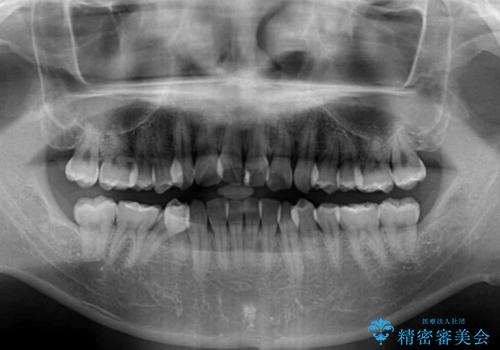

- 上下のデコボコと前歯のクロスバイトを改善したいとのことで来院された患者様です。

デコボコの程度は強かったのですが、口元の突出感はなかったため、非抜歯矯正としました。